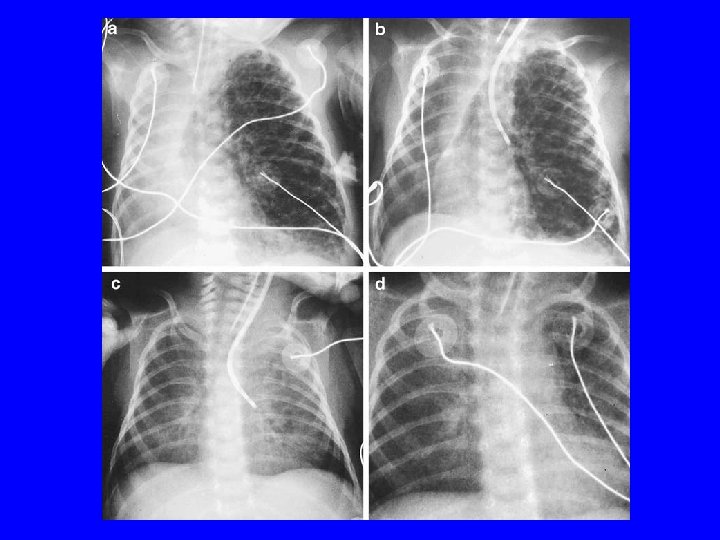

Air leak syndromes • Pneumothorax – Air between parietal and visceral pleura – Risk Factors-Aspiration (MAS), parenchymal diseases (RDS), PPV (high PIP) – Presentation can vary from • Tension: severe RD, bradycardia, apnea, hypotension with mediastinal shift • large leak: respiratory distress • small leak: usually accidental finding – Complication: IVH by ↓ venous return , SIADH – Diag. : asymmetrical air entry, transillumination – Rx: EMERGENCY if tension-needle aspiration followed by chest tube, supportive

• Pulmonary Interstitial Emphysema-air in interstitial space in the lung tissue – Usually preterm with RDS and on ventilation – Rx: decrease MAP, if unilateral-selective intubation/blocking of bronchus